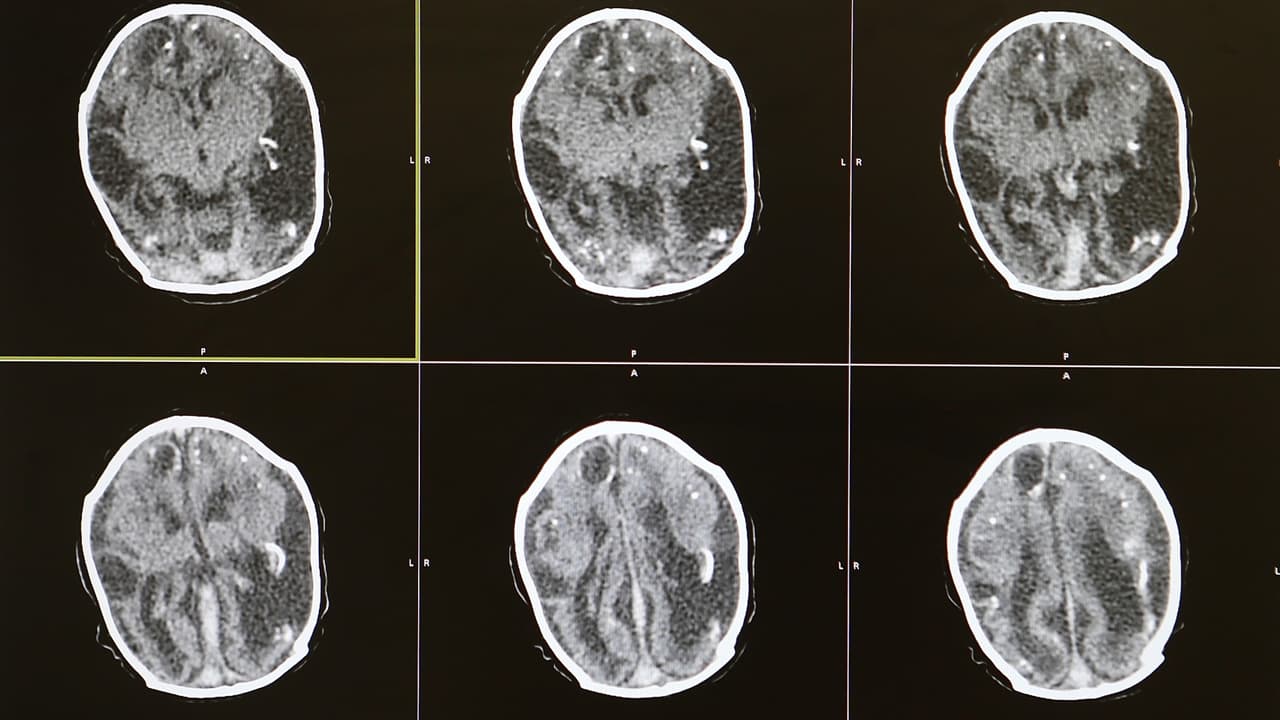

Según cifras, esta lesión es una de las principales causas de muerte y discapacidad en Estados Unidos. Expertos recomiendan visitar el doctor para identificar los factores de riesgo y así poder prevenir un derrame.